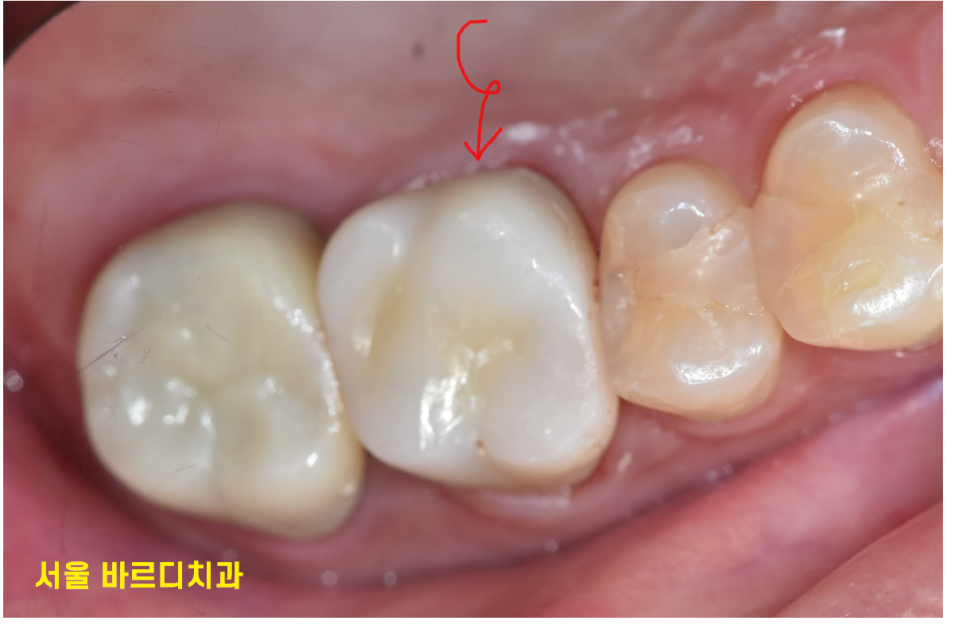

일반적인 신경치료 후에는 보철을 씌워

치아를 보호해주어야합니다.

치아가 부러지거나 약해지지 않도록요!

환자분은 뼈가 차고 있는지

지속 확인이 필요했습니다.

치료를 마친 후 환자분은 더 이상 통증을 느끼지 않으셨고,

문제의 치아는 정상적인 저작 기능을 되찾았습니다.

무엇보다 환자분께서 “자연치아를 유지하게 되어 정말 다행이다”라고 말씀하시며

만족감을 표현해 주셨습니다.